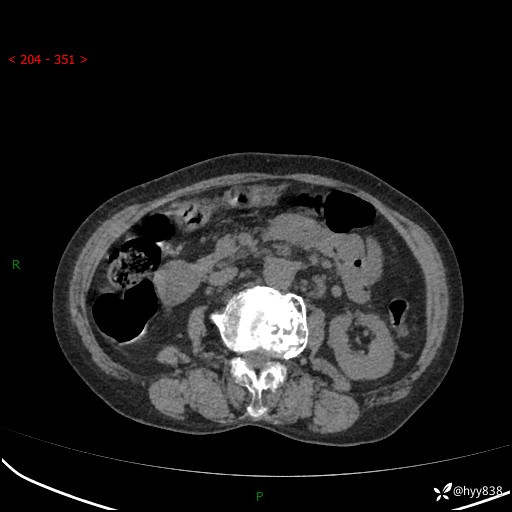

全腹部CT平扫